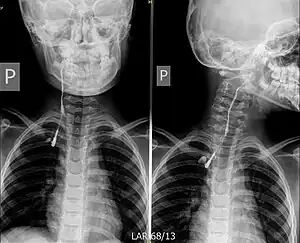

![]() | |

| Fistulogram (sinogram) of a right branchial cleft sinus. | |